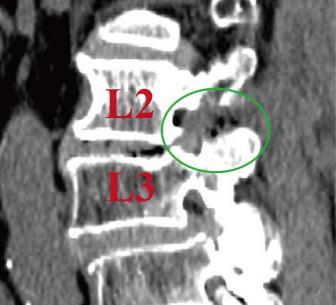

• 单通道非同轴脊柱内镜经椎间孔外入路(椎板外切迹)治疗极外侧椎间盘突出症的临床疗效观察

摘要:目的 观察单通道非同轴脊柱内镜经椎间孔外入路(椎板外切迹)治疗极外侧椎间盘突出症(FLLDH)的临床疗效。方法 回顾性分析2022年5月-2024年5月该院收治的,行单通道非同轴脊柱内镜经椎间孔外入路(椎板外切迹)治疗的FLLDH患者70例。于术前和术后,评估腰腿疼痛程度、腰椎功能和临床疗效。结果 相较于术前,术后3 d和3个月,患者下肢视觉模拟评分法(VAS)评分、腰部VAS评分、Oswestry功能障碍指数(ODI)、数字分级评分法(NRS)评分和Roland-Morris功能障碍问卷(RMDQ)评分明显降低,日本骨科协会(JOA)评分明显升高,差异均有统计学意义(P < 0.05);改良MacNab评分标准显示,末次随访时的优良率为94.28%。结论 单通道非同轴脊柱内镜经椎间孔外入路(椎板外切迹)治疗FLLDH,能明显改善患者腰腿疼痛和腰椎下肢功能,其具有创伤小、易操作、安全性高和疗效好等优点,值得在临床推广应用。